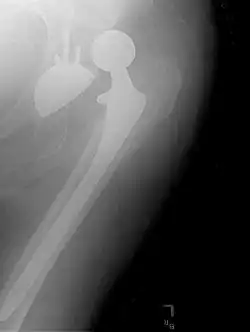

Hemiarthroplasty

Femoral (neck) offset is defined as the perpendicular distance between the intramedullary or longitudinal axis of the femur and the center of rotation of the native or prosthetic femoral head. An offset of less than 33 mm is associated with hip dislocation.[99][100]

Hemiarthroplasty is a surgical procedure that replaces one half of the joint with an artificial surface and leaves the other part unchanged. This class of procedure is most commonly performed on the hip after an intracapsular fracture of the femur neck (hip fracture). The procedure is performed by removing the head of the femur and replacing it with a metal or composite prosthesis. The most commonly used prosthesis designs are the Austin Moore and Thompson prostheses. A composite of metal and high-density polyethylene that forms two interphases (bipolar prosthesis) can be used. The monopolar prosthesis has not been shown to offer any advantage over bipolar designs. The procedure is recommended only for elderly/frail patients, due to their lower life expectancy and activity level. This is because over time the prosthesis tends to loosen or to erode the acetabulum.[101] Independently mobile older adults with hip fractures may benefit from a total hip replacement instead of hemiarthroplasty.[102]